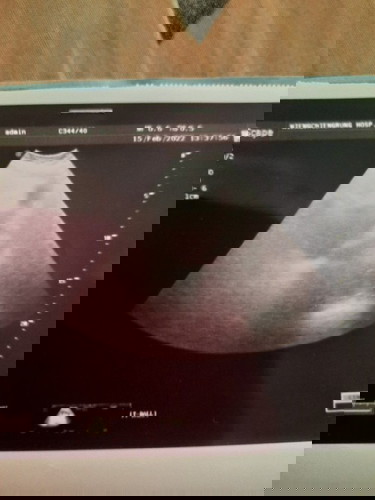

แม่ๆท่านไหนเคยมีประสบการณ์แบบนี้บ้างค่ะ อายุครรภ์6วีค แต่ไปซาวด์คุณหมอบอกไม่เจออะไรเลย

เราเพิ่งไปมา 6สัปดาห์3วัน ไม่เจอน้องค่ะแต่พบถุงการตั้งครรห์ ข้อดีคือท้องในมดลูกแต่ได้ของแถมคือเจอซีสมาอีก1ข้าง ให้เห็นแทนเจ้าตัวเล็ก 😅 คุณหมอนัด 15เดือนหน้าอีกที หมอว่า บางทีน้อยยังเล็กบวกกับคุณแม่รอบเดือนมาไม่ตรงวันตกไข่ก็อาจจะคาดไปไม่ตรงตามที่แม่นับ น้องเลยยังไม่โตพอจะเห็น รอเห็นน้องแล้วเขาจะดูจากขนาดน้องว่าสรุปแล้วอายุครรห์เรากี่สัปดาห์ หมอบอกเราแบบนี้

บ้านนี้เจอถุงตอน6wผ่านช่องคลอดค่ะ เพราะครรภ์ยังอ่อน ไข่อาจจะตกช้าด้วย ซาวด์หน้าท้องเลยไม่เจอ อย่าพึ่งเครียดนะคะ เดี๋ยวก็เจอ พอสัก7-8wก็เจอน้องแล้วจ้า ภ้าไม่มีการการปวดท้องหนัก เลือดออกก็หายห่วงค่ะ

ซาวทางหน้าท้องจะไม่ค่อยเจอ เพราะเล็กอยู่มาก ถ้าไม่รู้วันไข่ตกอาจไข่ตกช้ายึดตามรอบปจดไม่ได้ค่ะ แม่เองปจด23ตค64/ไข่ตก17พย64 เจอตัวน้อง30ธค64=6w4d เป็นไปได้ว่าไข่ตกช้าตอนนี้เพิ่งท้องแต่13w5dเอง😬

บ้านนี้ตรวจตอน 6 w หมอแจ้งมีแต่ถุงตั้งครรห์ ไม่เจอตัวเด็ก คาดว่าจะตั้งครรภ์ลม เลยเปลี่ยนหมอ ค่ะ ไปพบหมออีกท่านในวันเดียวกัน หมอบอกมีเสียงหัวใจเต้น ตอนนี้ 27 w แล้วค่ะ

บ้านนี้ไปตรวจตอน 5วีคคะ เจอแต่ถุงการตั้งครรภ์ในมดลูก ไม่เจอตัวเด็ก พอไปตรวจตอน 7w1d เจอตัวเด็กพร้อมการต้นของหัวใจจ้าา แม่ไม่ต้องเคลียดนะค้า